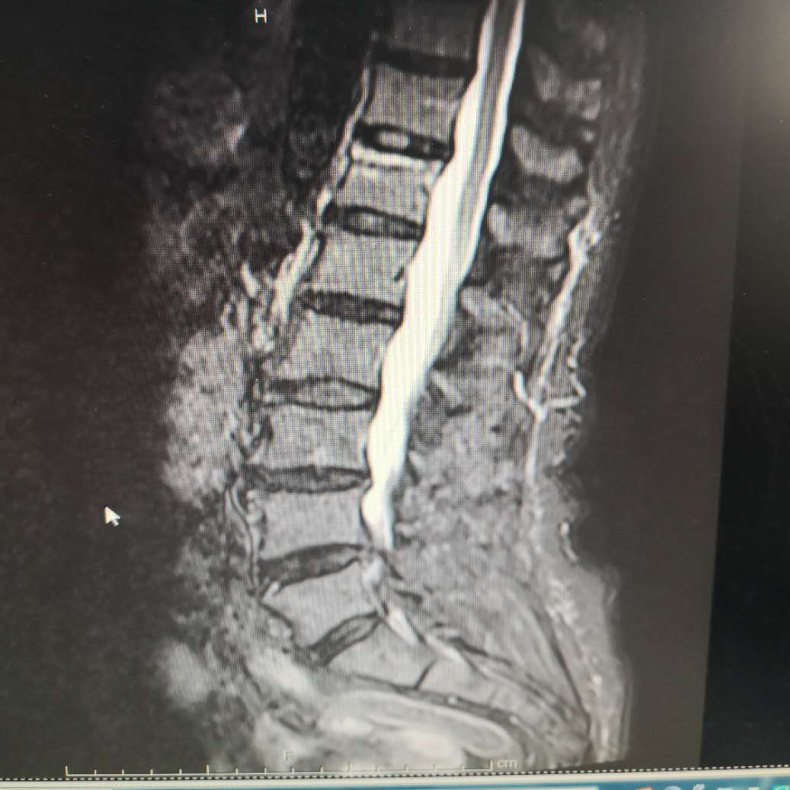

术前MRI

术后2周MRI